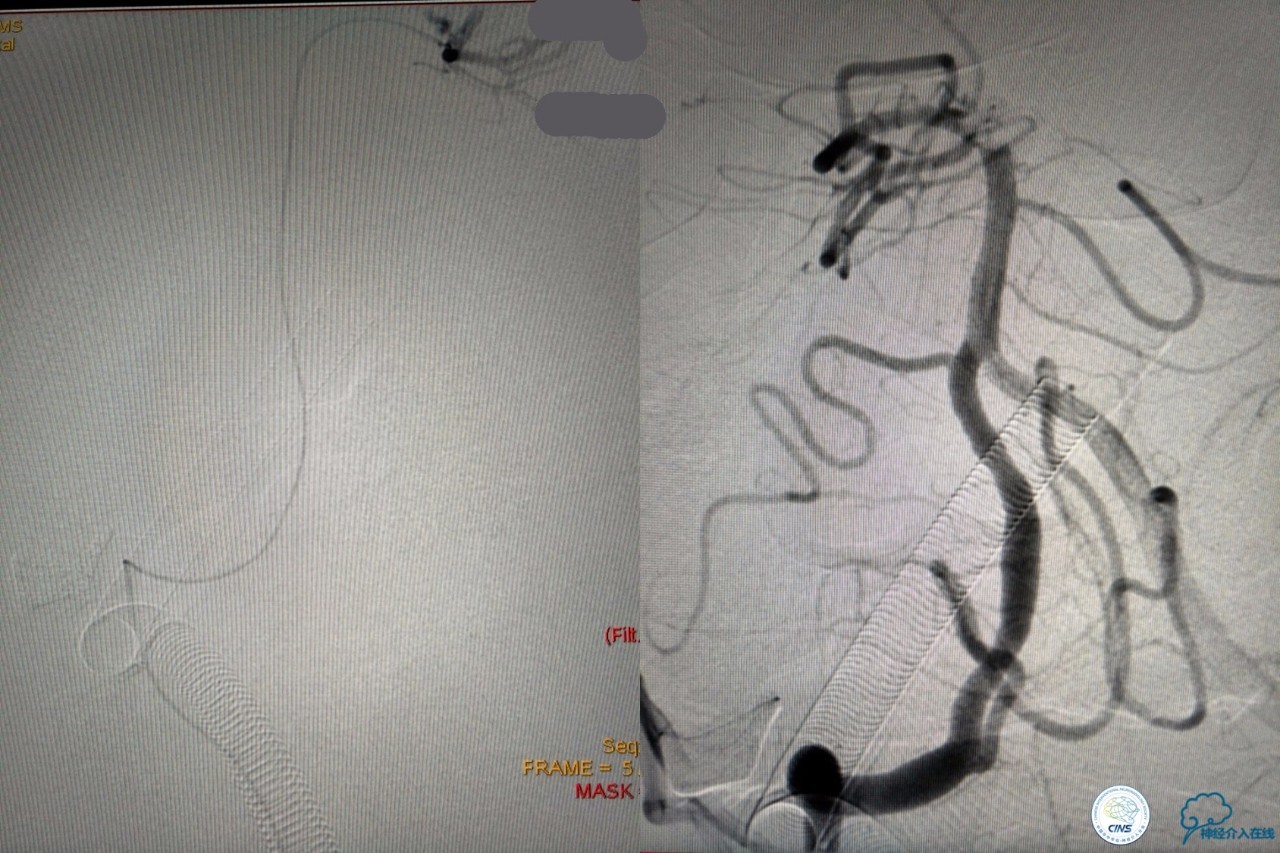

造影结果:右侧颈总动脉远端闭塞,前交通动脉开放,代偿方式:左侧颈内动脉→左侧大脑前动脉A1→前交通动脉→右侧大脑前动脉A1(反向)→右侧大脑中动脉供血区代偿。双侧大脑后动脉、右侧小脑上动脉及基底动脉顶端未见显影。

结合病史,体征及影像学,考虑患者本次发病为基底动脉尖急性闭塞,发病机制:栓塞?右侧颈总动脉慢性闭塞?非责任血管,且代偿良好,暂时不需处理!

6F导引导管到位至RV2远端,rebar-18微导管及transand微导丝至右侧大脑后动脉P1远端。

solitaireAB4-20mm支架取栓。